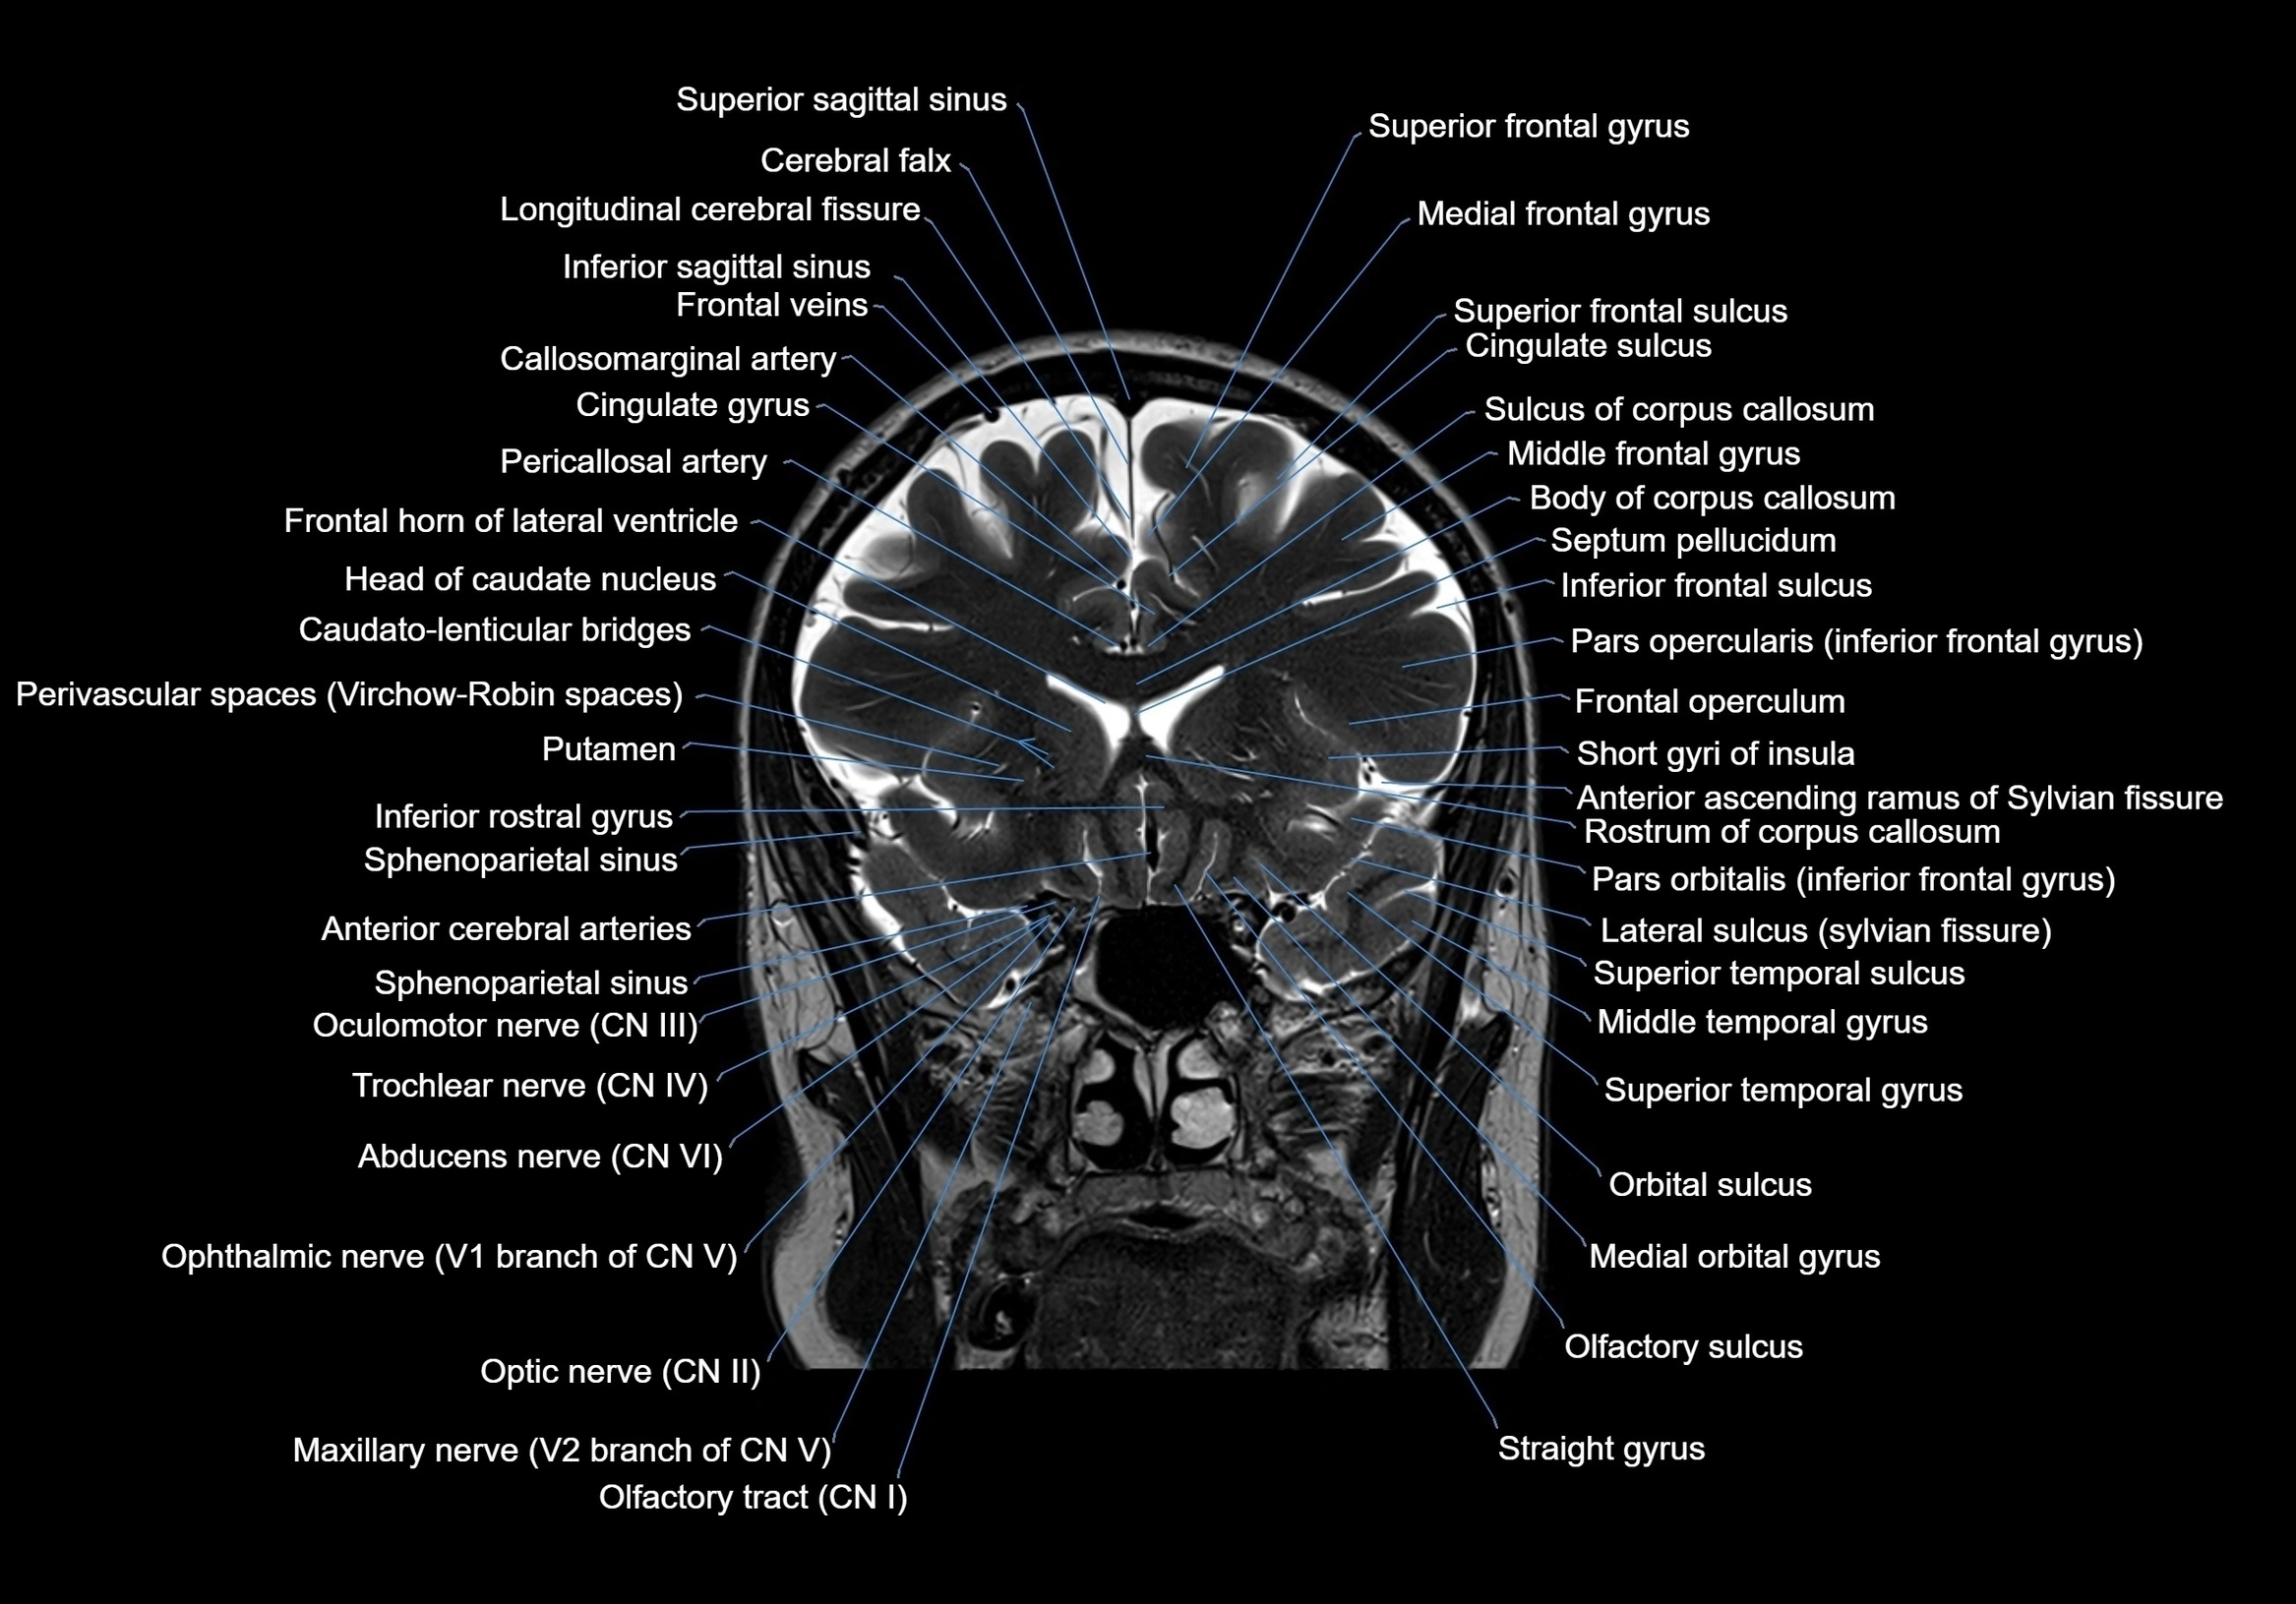

MRI images